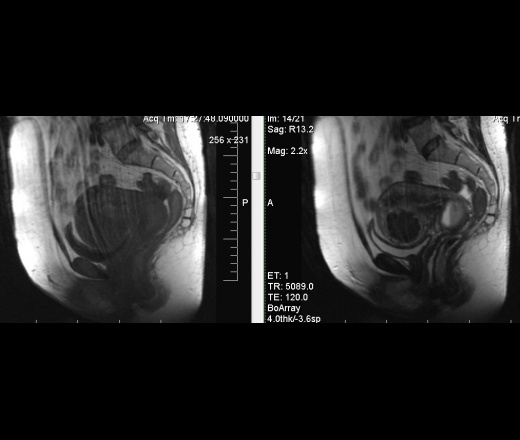

Содержимое эндометриоидных кист кровянистое. Уровни жидкость-жидкость очень характерны.

Может быть, это такая большая наботова киста с седиментацией ? Эндометриоидная по Т1 будет гипер, кажется? Еще миоматозный узел приличный.

Миому наблюдает в течении 4-х лет. Думал на наботову кисту, но таких размеров не встречал, в источниках не нашел. Так как толковее будет написать, коллеги? Эндометриоидная киста с гемораг-м сод-м? Наботова киста с седиментацией белка? Что правильнее будет?

Я бы написала эндометриодную.

Хачкурузов пишет, что Наботовы кисты не деформируют шейку матки, только эндометриоидные.